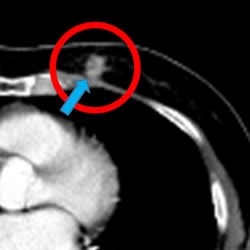

治疗前摄影图CT (治疗前:CT)

开始治疗后70日后(2个月半)(治疗 70天后)

*肺癌, 纵隔镜 淋巴结转移(71 岁男性)

来自中国的一名患者. 1疗程 5回 PD-1免疫抗癌剂(抗PD-1抗癌剂)

并用 免疫疗法NK・T细胞疗法 肿瘤减少了一半以上.

目前.以彻底消除肿瘤为目标.进行第2疗程的治疗.